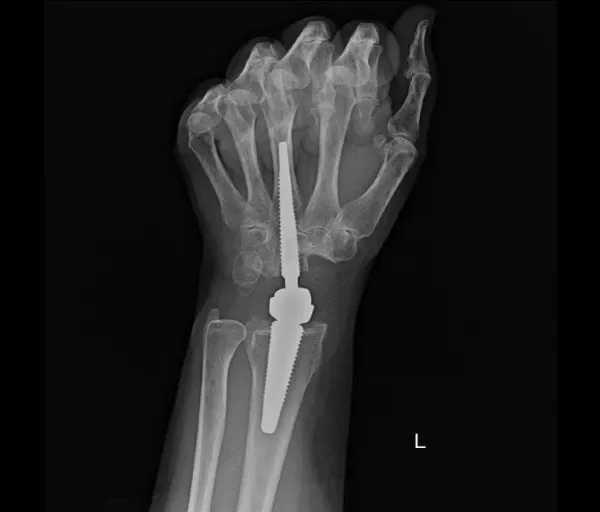

Polsartrose & Pisiformetriquetrale artrose

Wat is het?

Polsartrose is slijtage van het kraakbeen in één of meerdere polsgewrichten. Dit kan ontstaan in het:

- Radiocarpale gewricht (hand–pols)

- Midcarpale gewrichten

- Pisiforme–triquetrum gewricht

- DRUJ (spaakbeen–ellepijp)

Oorzaken zijn vaak: doorgemaakte breuken of ligamentletsels, doorgemaakte infectie, reumatische aandoeningen.

Chirurgisch

De keuze hangt af van:

- plaats van artrose

- ernst

- leeftijd

- activiteitsniveau / beroep

- Scaphoidectomie + four-corner fusieHet scaphoid wordt verwijderd, vier polsbeentjes worden vastgezetOngeveer 45% beweeglijkheid en 80% kracht blijft behouden

- Proximale rij carpectomieVerwijderen van scaphoid, lunatum en triquetrumNieuwe scharnierfunctie tussen capitatum en onderarmResultaten vergelijkbaar met four-corner fusieSoms aangevuld met een resurfacing-prothese

- Totale polsartrodeseHele pols wordt vastgezetVingers kunnen wel nog bewegenGeschikt voor zwaar belastend werk

- PolsprotheseVervanging van het polsgewrichtBewegingsbeperking blijft, maar voldoende voor dagelijkse activiteitenBelasting moet beperkt blijven om vroegtijdige slijtage te voorkomen

- DRUJ-protheseVervanging van alleen het draai-gewricht tussen spaakbeen en ellepijp

- PisiformectomieVerwijderen van het os pisiforme bij pijn in dit kleine gewrichtGeen verlies van polsfunctie